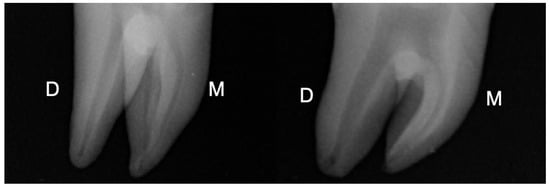

The Ethics committee of Saint Joseph University, Beirut, Lebanon provided the ethical approval (FMD184). Following a previous pilot study, sample size was determined for ensuring a power of 80% and α = 0.05 using G*Power 3.1.9.2 software (Heinrich-Heine University at Dusseldorf, Dusseldorf, Germany). Based on these parameters, a number of 10 samples for group was determined. Hence, a total of 20 intact human mandibular molars recently extracted for periodontal reasons were included. The selection criteria consisted of teeth with intact crowns exempted from fracture lines or cracks, caries, any previous restoration, and molars with one distal root with completely formed apices and an oval shape 5 mm below the root apex. This parameter was confirmed by periapical radiography in the mesial-distal (MD) and buccal-lingual (BL) directions. The canals were considered as oval when the BL diameter was 2.5 times larger than the MD diameter [12] (Figure 1).

Figure 1.

Periapical radiographs of two mandibular molars selected for the study. D: distal, M: mesial.